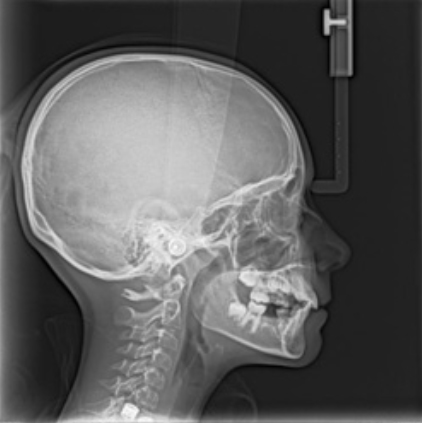

Cephalometric X-ray image

Performed in particular to define an orthodontic treatment plan. Cephalometric X-ray enables a very accurate diagnosis of orthodontic defects, allows for a precise assessment of facial growth and planning the appropriate correction of malocclusion, and at the same time the correct positioning of the teeth. This type of photos shows the soft tissues of the face and bone structures.